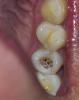

Scrabble Опубликовано 5 декабря, 2012 Поделиться Опубликовано 5 декабря, 2012 (изменено) jjts, а какого характера были боли, какие жалобы? Сфотографируйте зуб в сухом состоянии(по возможности) На этом зубе была пломба? Нерв ранее не удаляли из него? Изменено 5 декабря, 2012 пользователем Scrabble Ссылка на комментарий

jjts Опубликовано 8 января, 2013 Автор Поделиться Опубликовано 8 января, 2013 (изменено) К сожалению, вынуждена продолжать тему((( Поставили на зуб временную пломбу с пастой с кальцием. И вот на днях он сломался - внутренная стенка отломилась. Осталось две стенки зуба. Десна чуть припухшая. Беременность 27 недель. В то же время уже полтора месяца, как начались проблемы с зубом, не проходят сопли и постоянно болит горло. Фото зуба пока выложить не могу, так как не могу сама сфотографировать. Место, где зуб сломался, побаливает. Рентгеновского снимка нет, так как беременная. К стоматологу пойду на днях, так как сейчас одна дома с ребенком. И вот у меня такие вопросы:1. Зуб однозначно на удаление? Если да, используется ли при удалении рентген? Надо ли после удаления пить антибиотики?2. Если зуб, при оценке возможности стоматологом, все-таки возможно спрятать под коронку, процесс установки вкладки и коронки тоже сопровождается рентгеном? Нельзя ли это отложить после беременности, а пока ходить со сломанным зубом, или этот сломанный зуб, вернее, оголенная десна будут источниками инфекции и дальше?У меня уже за эти полтора месяца болезни сложилось четкое ощущение, что постоянная простуда и зуб связаны, но терапевты советуют ограничиться полосканиями всякими, а я уже думаю, что мне нужны антибиотики, так как по моим ощущениям у меня непроходящая инфекция, которая "курсирует" от горла и носа к зубу. Вот опять пойду после праздников в поликлинику, но там мне кроме биопарокса ничего не назначают(((P.S. Как придет муж с работы, постараюсь выложить фото, сама себя не могу запечатлеть Изменено 8 января, 2013 пользователем jjts Ссылка на комментарий

jjts Опубликовано 8 января, 2013 Автор Поделиться Опубликовано 8 января, 2013 (изменено) Если зуб скололся ниже уровня десны - это может оценить врач - то удалять. Если Вы отказываетесь от снимка - никто не может Вам его навязать, вообще по стандартам, любая стоматологическая манипуляция - лечение, удаление, протезирование должны сопровождаться диагностикой. Антибиотики, как правило, назначают при гнойном воспалении.спасибо. Вообще я не то чтобы отказывалась от снимков, мне сами врачи отказываются их делать. Я-то думала, у них визиограф, так как видела через открытую дверь в рентген-кабинет, что там монитор. Но сегодня врач сказал, что у них не визиограф, а ренгент, просто изображение выводится на монитор. А сегодня в итоге прочистили каналы, че-то туда вставили, что-то типа штифта, но не штифт, я так поняла, какой-то штырек стальной, и нарастили зуб пломбой, а сам его подточили, чтобы в жевании не участвовал. И снова отправили гулять до "после родов". Буду надеяться, что дохожу до родов и чуть после, и потом уже буду делать коронку. Изменено 8 января, 2013 пользователем jjts Ссылка на комментарий

jjts Опубликовано 14 января, 2013 Автор Поделиться Опубликовано 14 января, 2013 Уважаемые врачи! Опять я здесь. Завтра будет неделя, как лечили зуб (беременность, заболел зуб, оказалось, что он внутри мертвый, ставили сначала лекарство, потом временную пломбу, потом зуб сломался, поставили кусочек стомат. инструмента, нарастили пломбой, чтобы лечить уже после родов. Зуб 5-ка). Все делали без рентгена - говорили, что нельзя, хотя рентген в клинике есть. Сначала зуб чувствовал себя отлично. Сначала поныл пол-суток,на вторые-третьи сутки все было отлично. На 4-е и 5-е сутки - опять нытье, причем ноют и соседние зубы, и зубы вообще с другой стороны. Сегодня с утра было все снова отлично, чуть ныть стало только после пребывания на улице - то есть на холоде. Есть не больно. А если ударять краем карандаша по пломбе, где-то внутри чувствуется несильная, но противная боль. Вообще у меня было так, что после постановки маленькой пломбы один зуб ныл месяц примерно, потом все прошло, пломба эта сидит уже лет 5 без происшествий. Так что списывала боль в зубе на нормальную боль после вмешательства. Может быть именно такое?Но уже созреваю к тому, чтобы идти в другую клинику, где меня все-таки "сфотографируют" несмотря на беременность. Вот в процессе обзвона одной из клиник сказали, что у них не рентген, а ортопантограф. Это что за зверь? То же самое, что и визиограф? Или тот же самый рентген? Сказали, что снимок могут даже выслать на электронную почту - такое и вправду может быть? Ссылка на комментарий